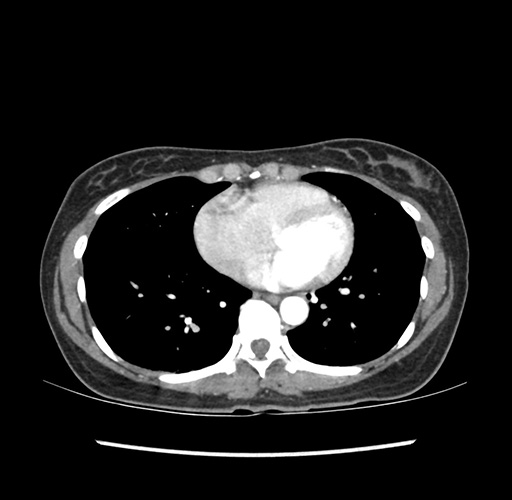

Imaging Analysis

Look through the patient's CT scan to identify any areas of concern for the necessary procedure.

Based on your CT findings, which issue(s) would give reason for "planned slowing down moment(s)" in this case?

Considering a standard left lateral sectionectomy procedure, what step(s) of the operation would you do differently in this case ?